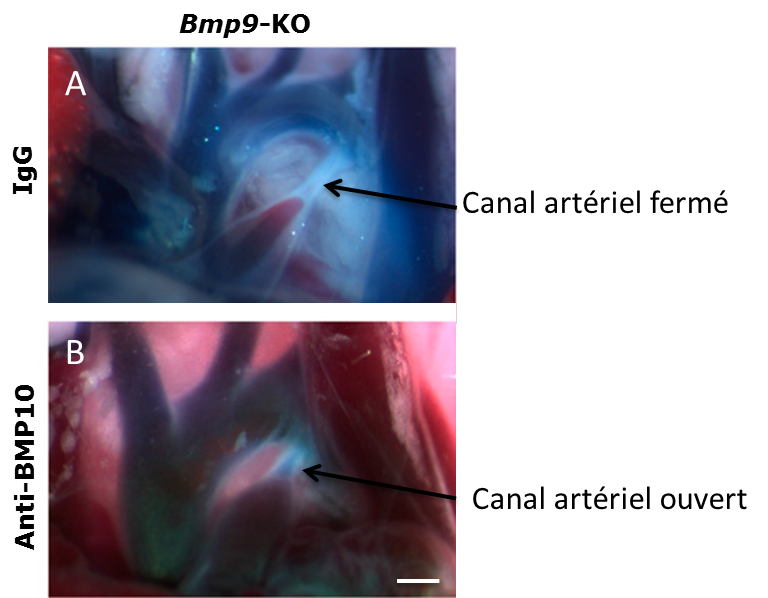

Une équipe du CEA-IRTSV, en collaboration avec le CHU de Grenoble, a découvert le rôle majeur de deux protéines dans la fermeture du canal artériel. D’autres études avaient déjà révélé l’importance de ces protéines, appelées BMP9 et BMP10, dans la signalisation cellulaire liée aux systèmes sanguins et lymphatiques1. « Des souris dont le gène (et donc la protéine correspondante) BMP9 est déficient présentent une fermeture anormale du canal artériel, explique Sabine Bailly, chercheuse au CEA-IRTSV. En outre, le blocage de BMP10 chez les souriceaux obtenu par l’addition d’un anticorps anti-BMP10 empêche le remodelage de ce canal et entraîne la réouverture du canal artériel. » Les chercheurs ont réussi à montrer qu’une étape de transformation cellulaire nécessaire à ce remodelage implique BMP9 et BMP10. Aussi, ils sont parvenus à identifier chez deux patients présentant une PCA des anomalies dans une région du génome humain comprenant 8 gènes, dont celui codant pour BMP10. Suite à ces résultats, de nouvelles perspectives thérapeutiques pour traiter les enfants atteints de cette pathologie pourraient voir le jour.

Tronc aortique de souriceaux de 5 jours après injection de bleu Evans dans le cœur. Souriceaux Bmp9-/- injectés à jour 1 et 3 après la naissance avec IgG (A) ou un anticorps neutralisant dirigé contre BMP10 (B). Echelle (500 µm). © CEA